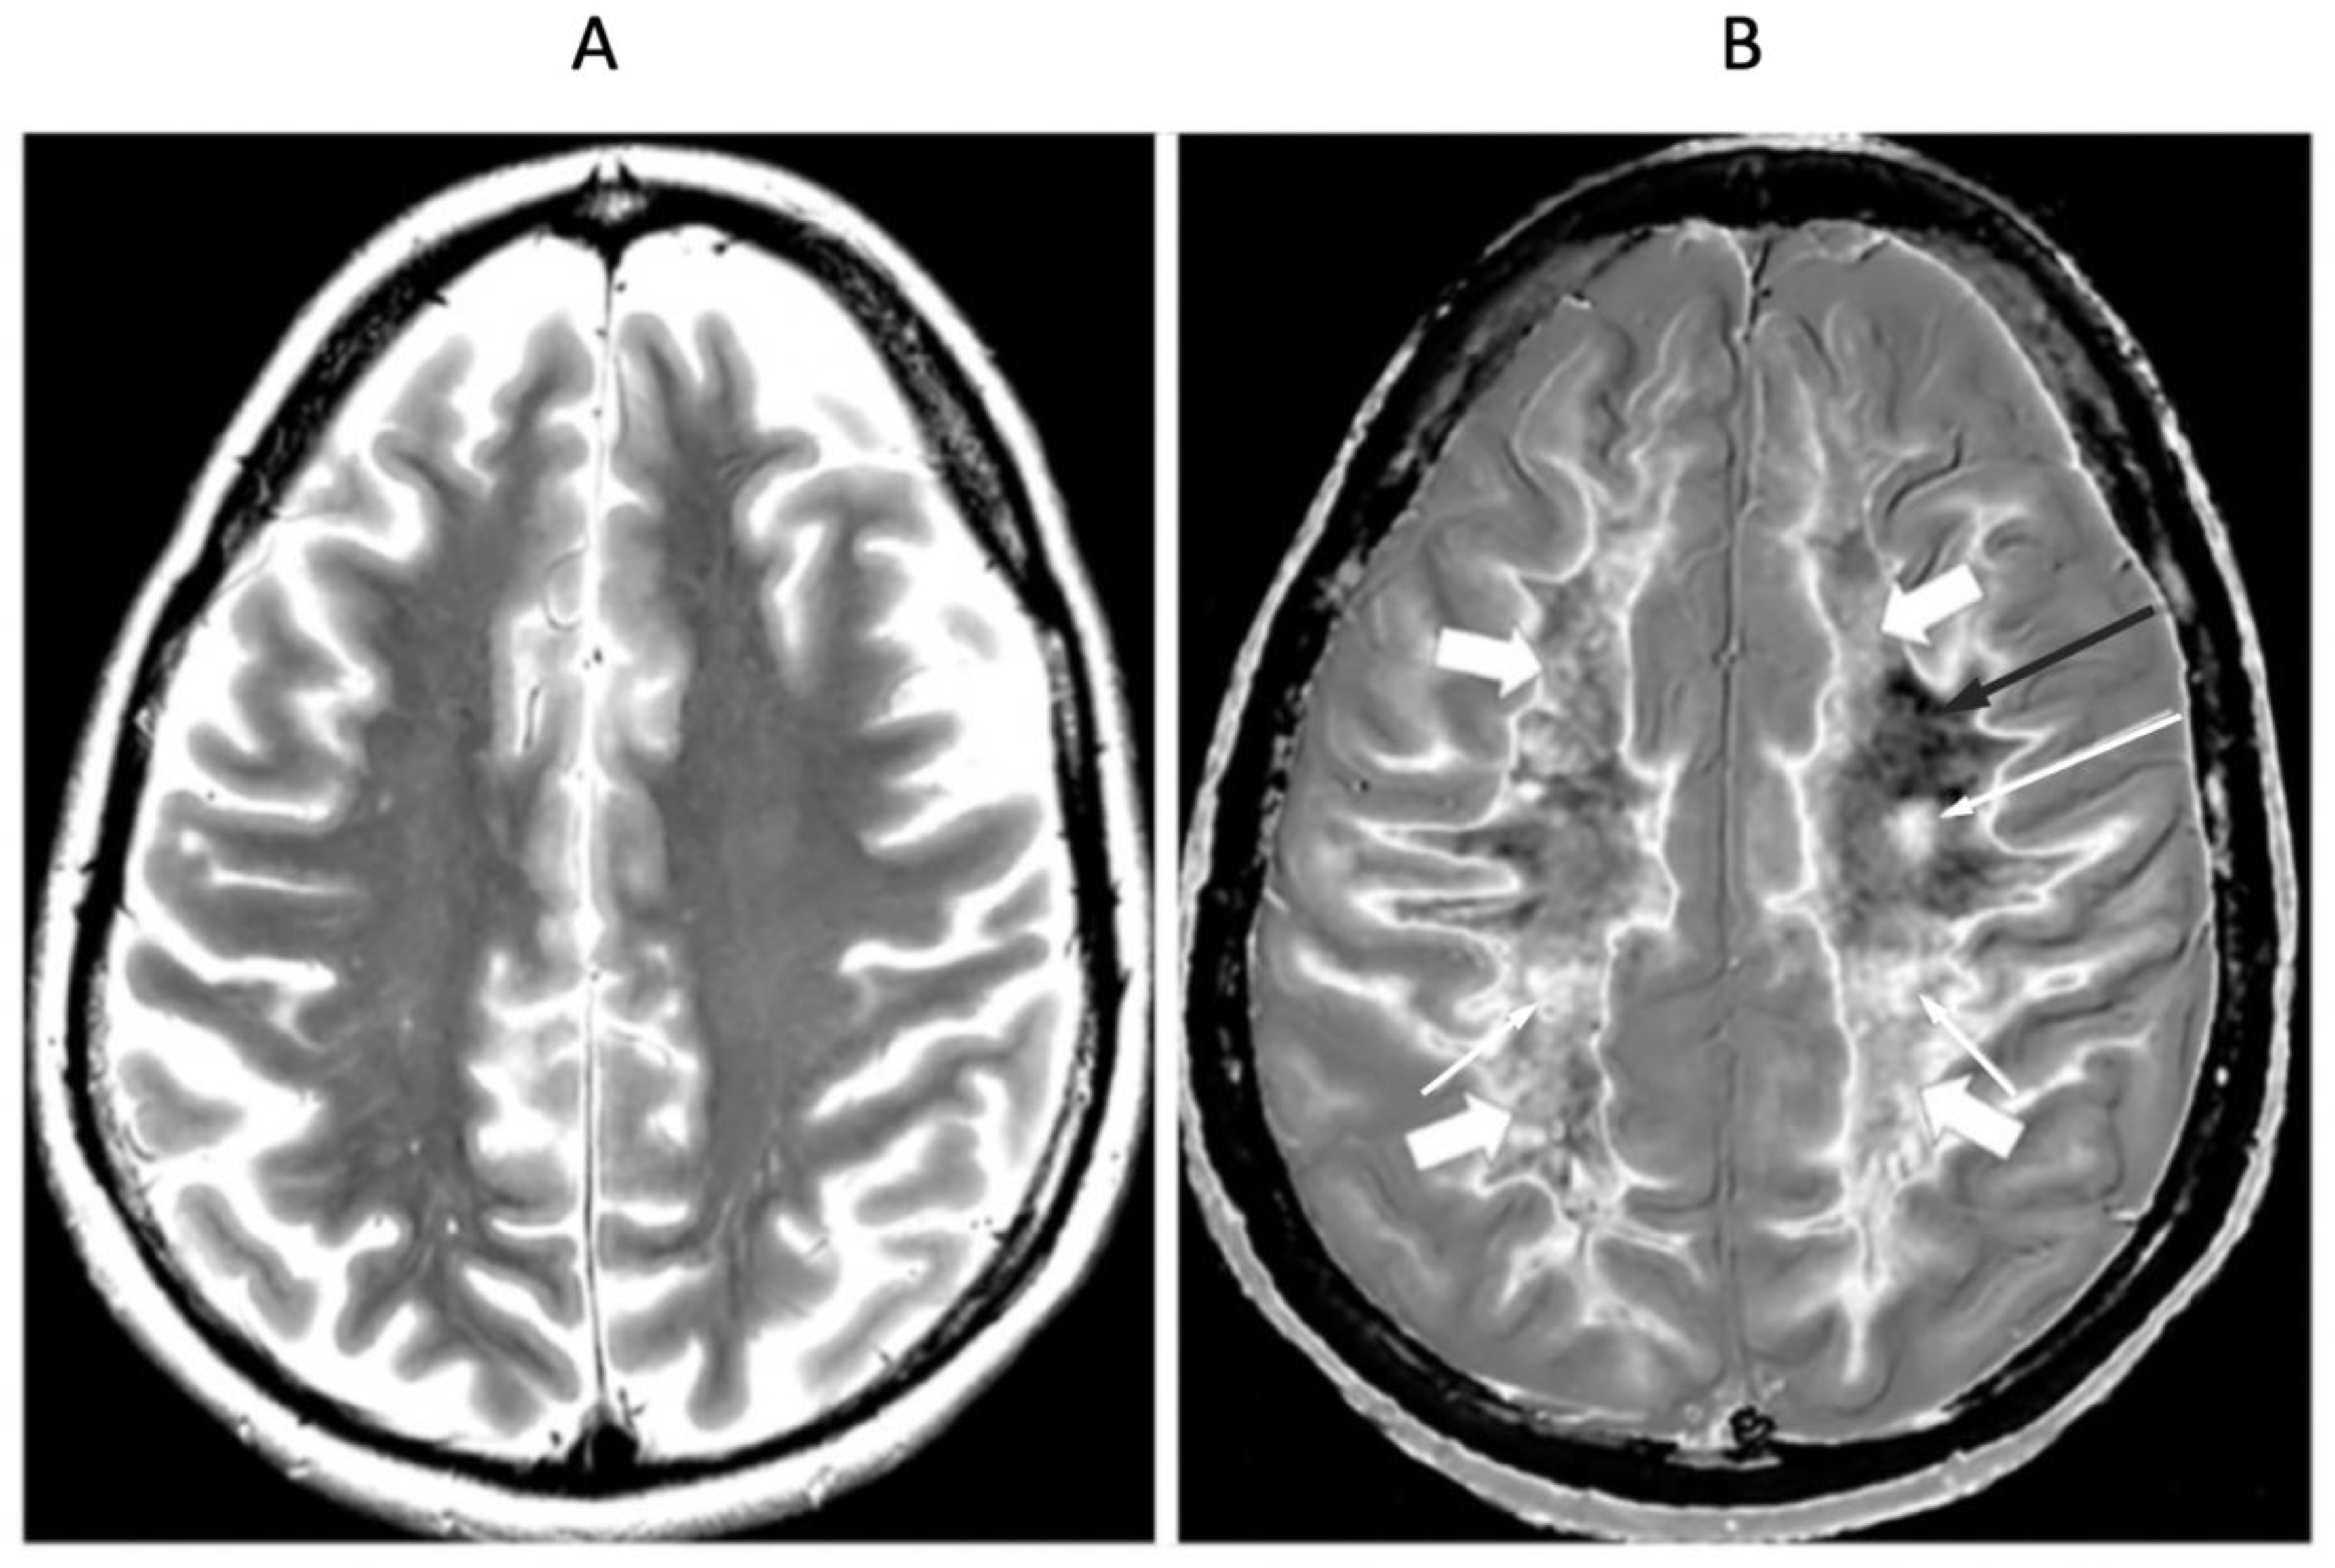

Multiple Sclerosis (MS)

Focal lesions, as well as patchy white matter changes, may be seen in areas that appear normal on T

2-wFSE images in a patient in remission (

Figure 15) (compare with normal low signal appearance of normal peripheral white matter in

Figure 1B). In another case during a relapse, one lesion is seen on the T

2-FLAIR image in

Figure 16A (long arrow). This lesion is also seen in

Figure 16B (long arrow). There are an additional six lesions (small arrows) in

Figure 16B. Five of the lesions in

Figure 16B have high signal boundaries. This can be due to a large increase in T

1 in the lesion beyond the peak of the bipolar T

1-filter or a decrease in the abnormal T

1 in the lesion due to the presence of paramagnetic free iron. Two of the lesions with high signal boundaries shown in

Figure 16B have paramagnetic rim signs on the filtered susceptibility weighted images (arrows,

Figure 16C). The high signal boundaries seen on some MS lesions may be a sign of disease activity.

In addition, there are widespread abnormal areas in white matter which are only seen on the dSIR images (

Figure 16). These changes are typically bilateral, symmetrical and have an increased signal. They have the features of a whiteout sign (

Figure 16B) and to date have only been seen in patients with MS during a relapse.

Figure 16.

32-year-old female with MS during a relapse. T

2-FLAIR (A), synthetic narrow mD dSIR (T

1-BLAIR) (B) and filtered gradient echo (C) images. On the T

2-FLAIR image (A), one lesion is seen (long arrow). The surrounding white matter appears normal. On the T

1-BLAIR image (B), the lesion shown on the T

2-FLAIR image is seen with a high signal boundary (long arrow) as well as six other lesions four of which also show high signal boundaries or bubble signs (short arrows). Two of the five high signal lesions show paramagnetic rim signs on the filtered gradient echo image (arrows) in (C). In addition, most of the white matter in (B) is high signal corresponding to a high grade 4/5 whiteout sign [

1]. No whiteout sign is seen on the T

2-FLAIR image (A).